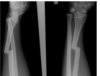

abnormalities

A

• spiral fracture midshaft ulna

• ulna fracture is displaced and angulated

• dislcation proximal radius